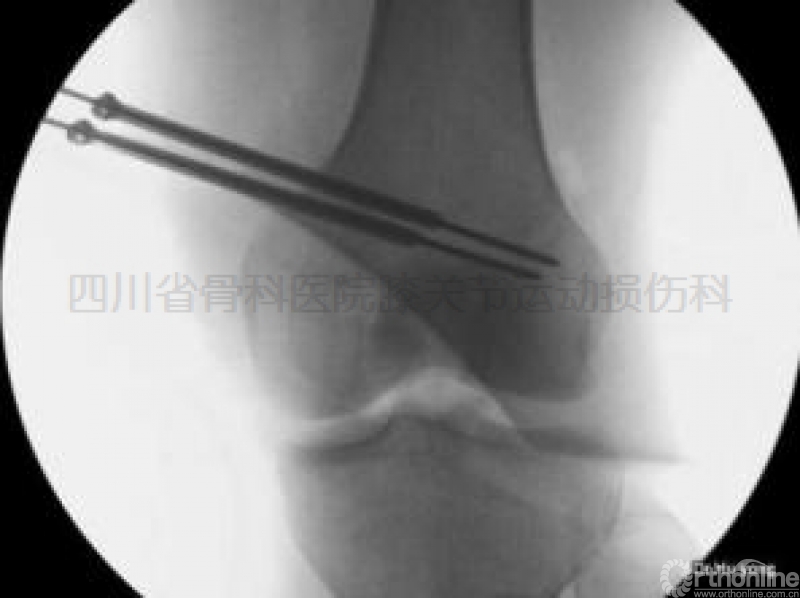

②导针推送鞘管到达正确的位置(图示六);

图示六经前内入口安全区逆向横穿RigidFix导针、鞘管击入到位后X线透视所见。